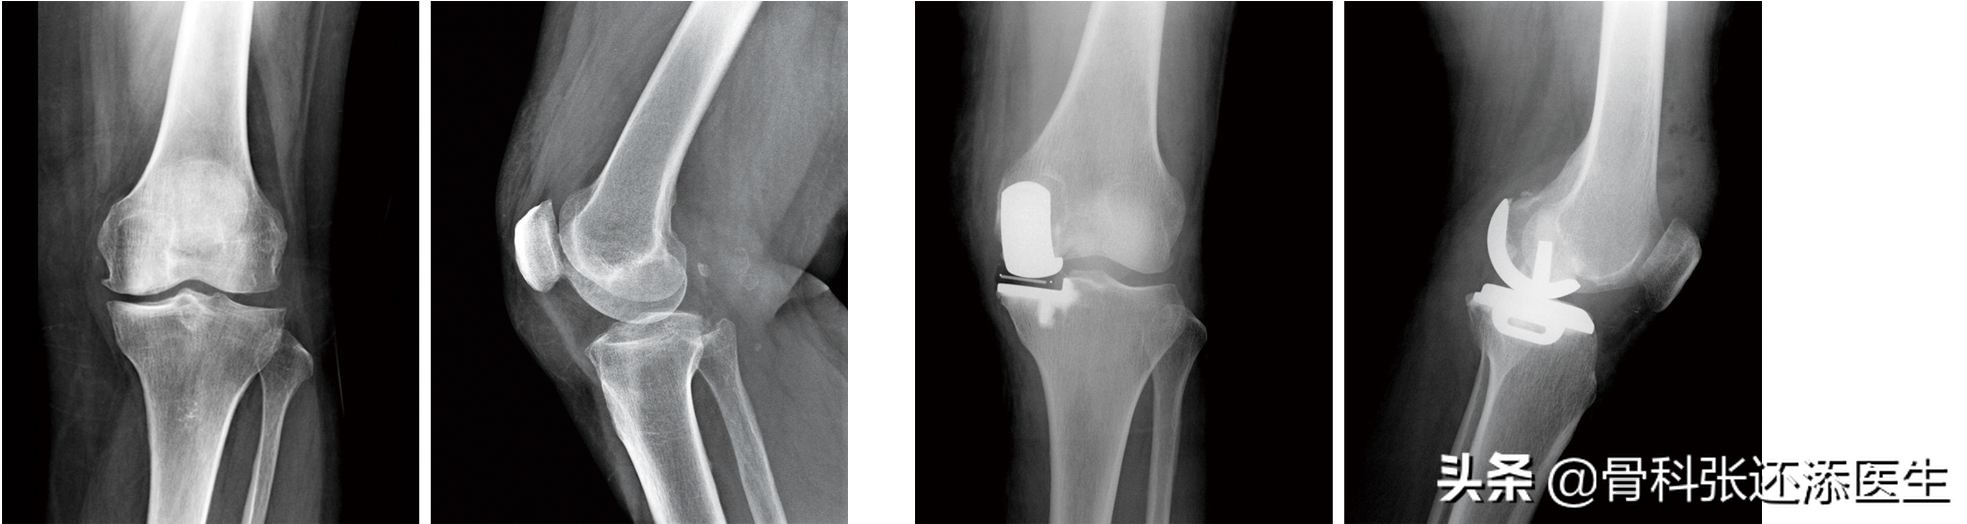

膝关节部分置换术:这是说单个膝关节,只有一侧磨损退变严重(比如内侧磨,外侧还好,髌骨软骨面也可以),这时可以微创治疗单髁,不用整个膝关节置换。

人工膝关节置换术:膝关节置换,换一个新的人工关节。现在的人工关节都很稳定耐用,已经是外科非常成熟的手术。

总结:膝骨关节炎晚期的病人,膝关节严重受损,需要进行置换,换上坚固的人工关节。

左2图术前,右2图单髁置换术后